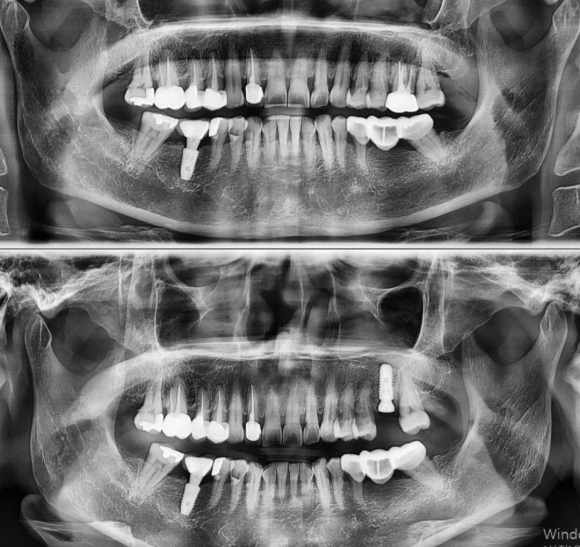

2022.3.2 구치부 발치 후 즉시 임플란트 #상도동에서임플란트가장많이하는치과

2022.3.2 구치부 발치 후 즉시 임플란트